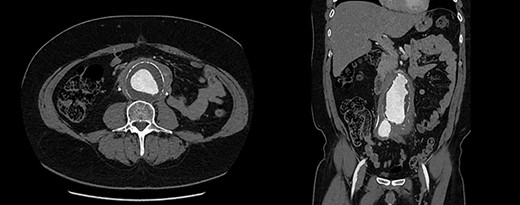

Urgent ureteric stenting to treat ureteric obstruction was performed with rapid normalization of renal function following stent insertion (Fig. 2). Upon normalization of his renal function, a contrast CT aortogram (CTA) was performed to delineate a 61 × 64 mm AAA, bilateral common iliac aneurysms (right 41mm × 44mm, left 31mm × 36mm) and associated peri-aortic stranding (Fig. 3).

CTA demonstrating (A) a large 61mm × 63mm infrarenal AAA and (B) bilateral common iliac aneurysms (right 41mm × 44mm, left 31mm × 36mm).